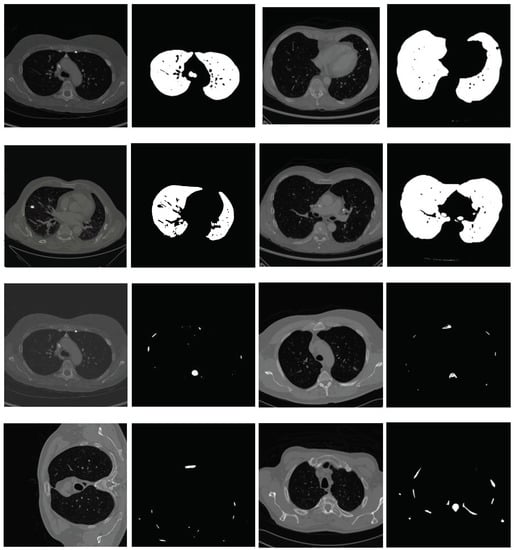

2.2. Lung Segmentation

2.2.1. Segmentation in Lung Window

2.2.2. Segmentation in Mediastinal Window